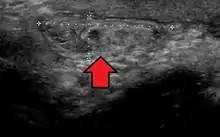

Inguinal

By far the most common hernias (up to 75% of all abdominal hernias) are inguinal hernias, which are further divided into the more common indirect inguinal hernia (2/3, depicted here), in which the inguinal canal is entered via a congenital weakness at its entrance (the internal inguinal ring), and the direct inguinal hernia type (1/3), where the hernia contents push through a weak spot in the back wall of the inguinal canal. Inguinal hernias are the most common type of hernia in both men and women. In some selected cases, they may require surgery.